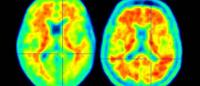

Columbia researchers have discovered a genetic variant that reduces the odds of developing Alzheimer’s disease by up to 70% and may be protecting thousands of people in the United States from the disease.

The discovery of the protective variant, which appears to allow toxic forms of amyloid out of the brain and through the blood-brain barrier, supports emerging evidence that the brain’s blood vessels play a large role in Alzheimer's disease and could herald a new direction in therapeutic development.

Fibronectin is usually present in the blood-brain barrier in very minute amounts, but it is increased in large amounts in people with Alzheimer’s disease. The variant identified in the fibronectin gene seems to protect against Alzheimer’s disease by preventing the buildup of excess fibronectin at the blood-brain barrier.